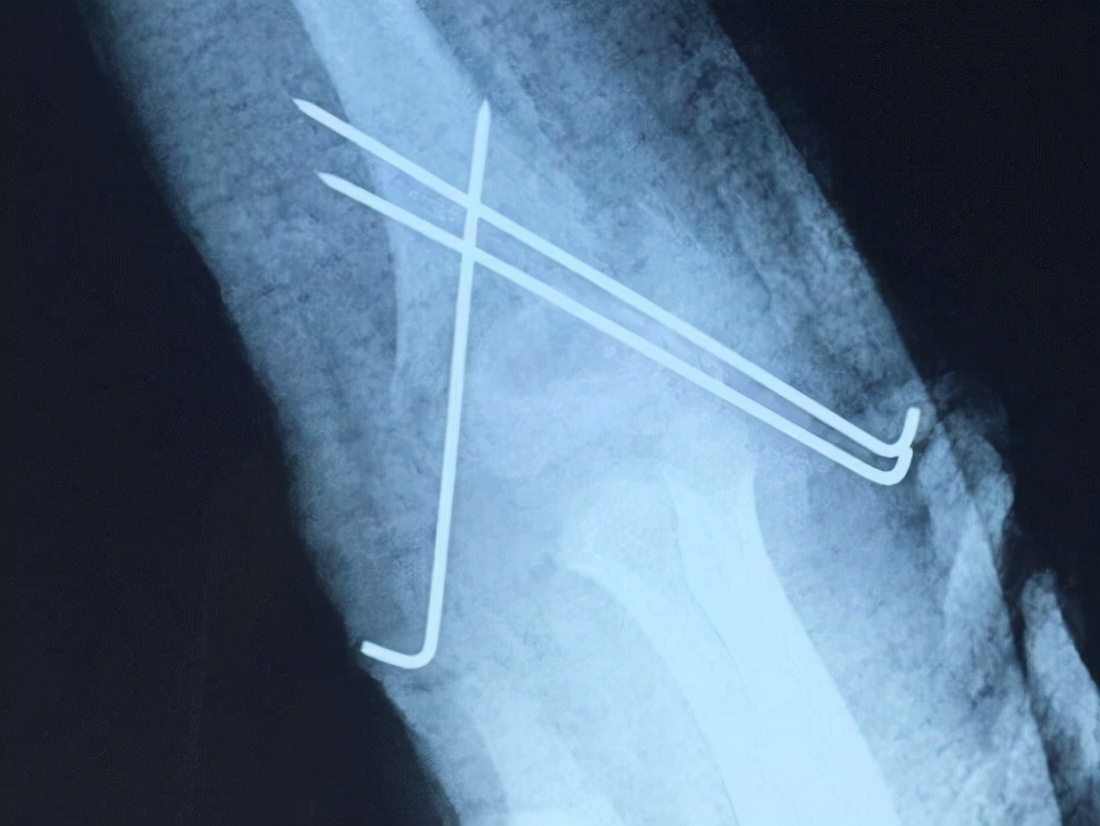

肘关节骨折后保守治疗的适应证 保守治疗的主要方法就是手法复位,然后用石膏、克氏针等方式在合适的体位下实施制动和固定,以确保骨折部位得到最佳固定并逐步愈合。保守治疗的优点是不会增加创口,但可能需要更长时间的制动,且不能保证精确的断端对线。肘关节骨折后,如果断裂的骨块无明显错位、无重要血管神经损伤、无软组织嵌入者,可实施保守治疗。另外,如果存在年龄大、骨质差、全身健康情况差、手术预后不佳、肘关节外部皮肤有感染等问题,应优先选择保守治疗。